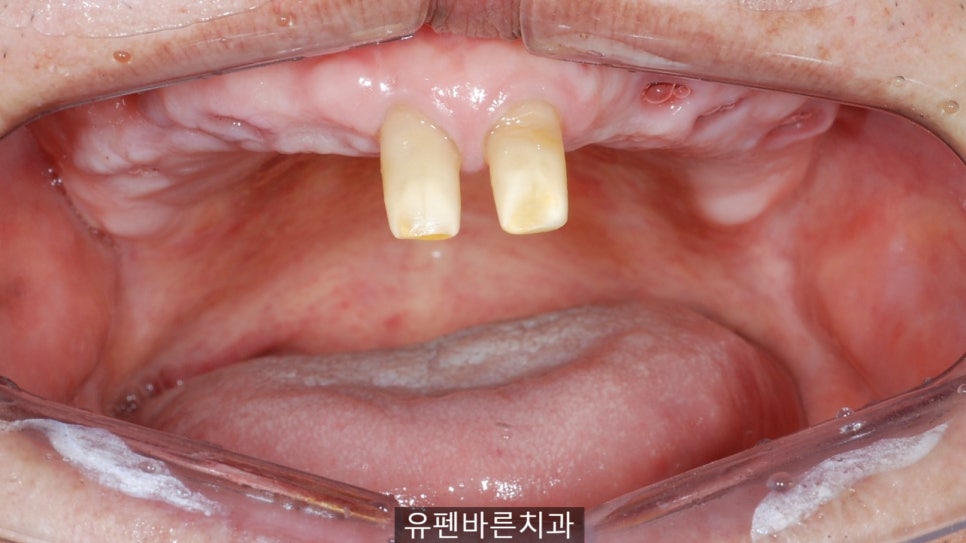

먼저

잇몸 절개 후

뼈 상태가 양호한 곳에

임플란트 위치를 잡고

수술을 시작하셨는데요,